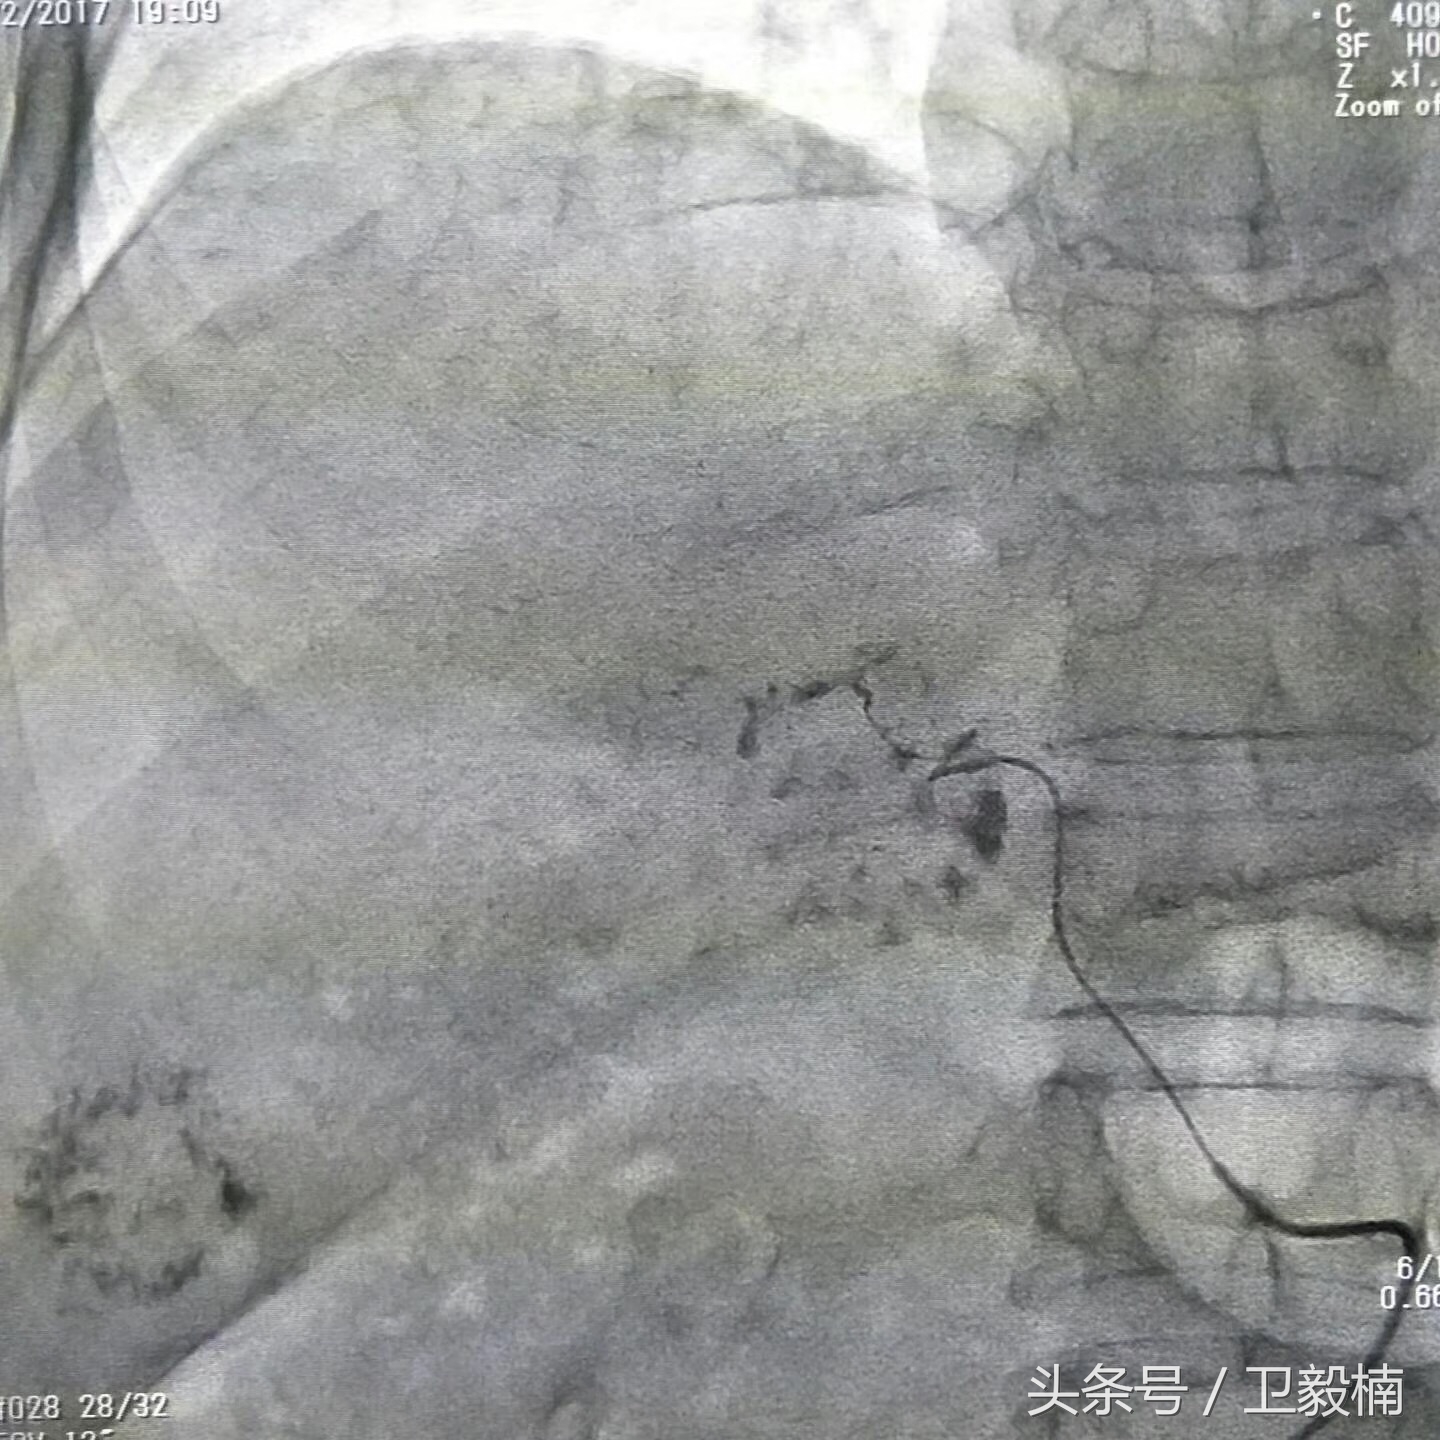

栓塞过程